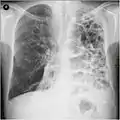

A chest X-ray is not useful to establish a diagnosis of COPD but it is of use in either excluding other conditions or including comorbidities such as pulmonary fibrosis and bronchiectasis. Characteristic signs of COPD on X-ray include hyperinflation (shown by a flattened diaphragm and an increased retrosternal air space) and lung hyperlucency.[5] A saber-sheath trachea may also be shown that is indicative of COPD.[111]

Lung bulla as seen on chest X-ray in a person with severe COPD